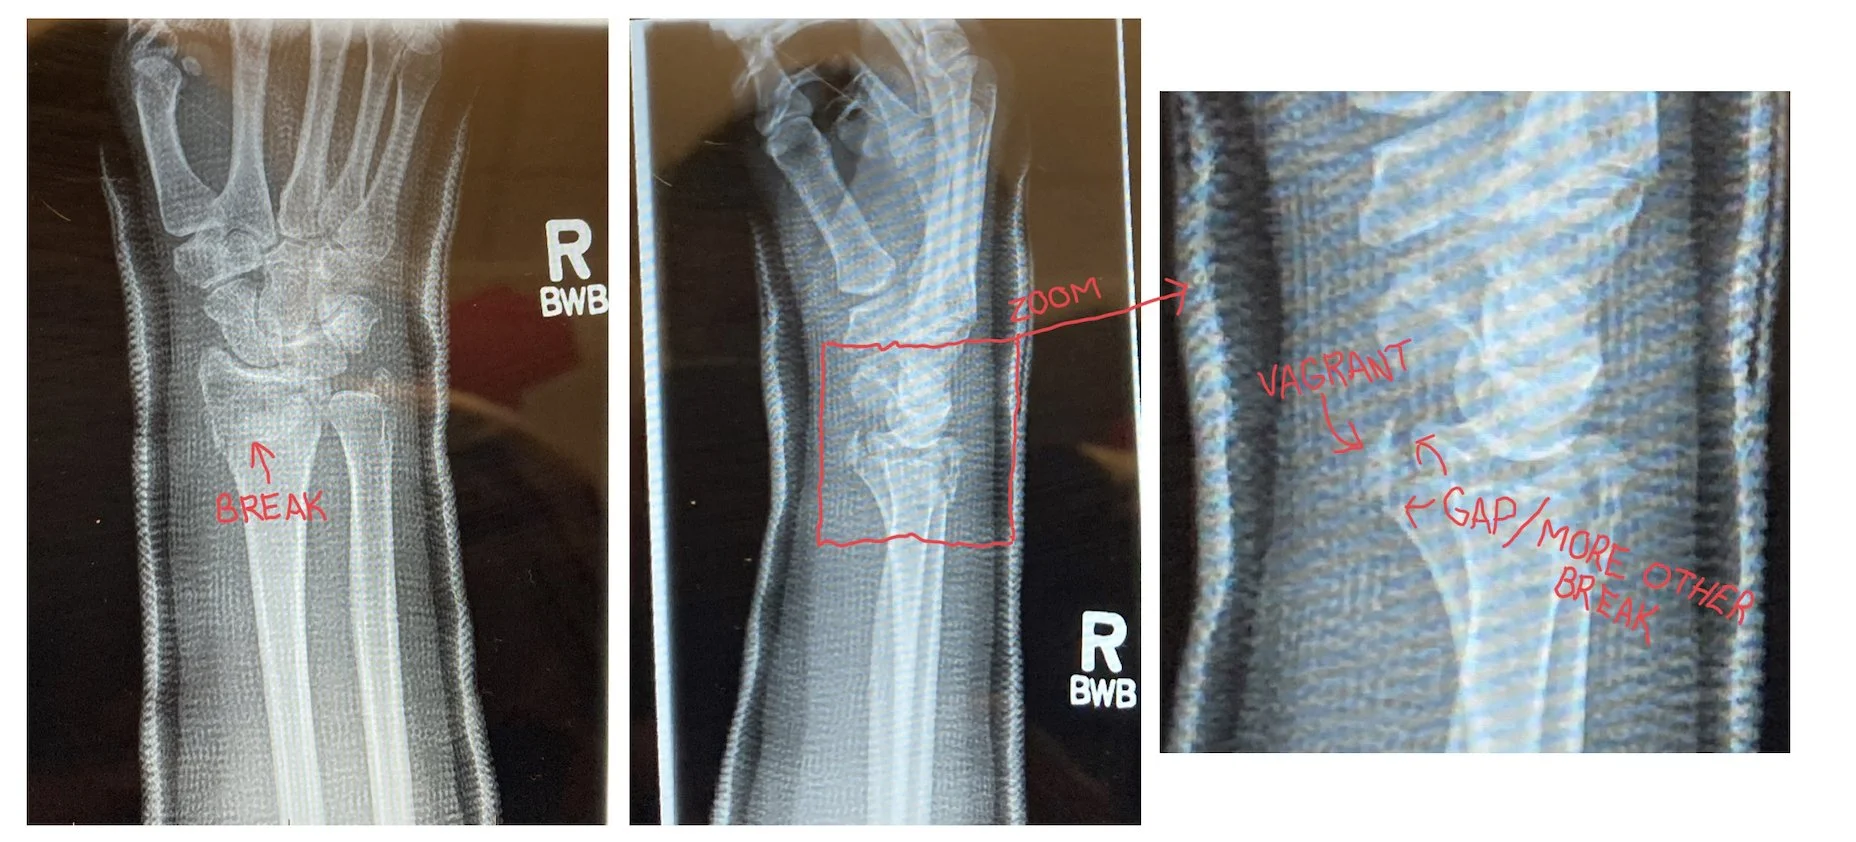

(Apologies for the reflections and satiations — the official copies didn’t arrive in time, so these were photographed from another screen because the program they were being viewed in blocks screen shots.)

Unlike in my edited doodle, there was not a single break, clean and easily fixable — there were multiple breaks, with one piece of bone sitting all alone, isolated from its friends, even after they sedated me and “reduced” it (we common folk usually say “set”). I am eternally grateful that I was 100% unconscious for that part.

When I woke up from the anesthetic a cast had been applied (you can see it’s ghostly image in the x-rays above) and I was ultimately sent home, with an appointment to see an orthopaedic surgeon for an assessment ten days later. Normally the wait for the specialist would have been shorter, but I’d made the mistake of falling too late in the day, and with the terrible road and sidewalk conditions there had been a lager than usual occurrence of broken bones, most of which had been processed before me. It was a sleepless, drugged up, painful ten days.